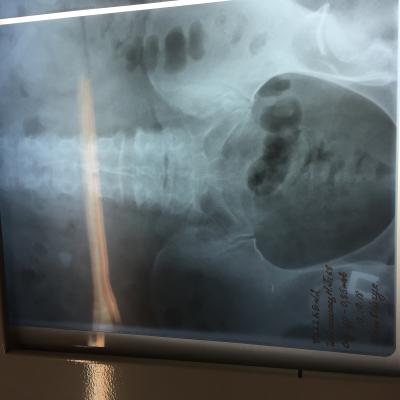

Камень в почках размер 25 мм

Беспокоила тяжесть в почке и периодические боли, часто выходили мелкие камни, после очередного приступа обратилась к врачу и попала в Больницу, сделали снимки ( фото прилагается) обнаружен крупный камень размером 25 мм и несколько мелких . Что делать? Не знаю? Дайте пожалуйста рекомендации!!! Удалять камень? Каким способом операция либо новыми технологиями это возможно?